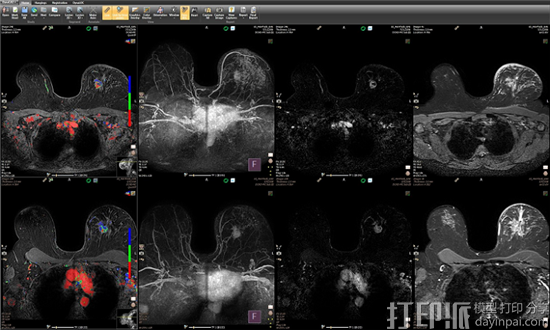

今天,全球健康科技领导者Royal Philips宣布推出IntelliSpace Portal 10,这是一款先进的可视化和量化平台。新一代的解决方案具有强化功能,特别关注肿瘤学,为放射科医生提供改进的全套应用和工作流程,以支持复杂肿瘤病例的研究和追踪。IntelliSpace Portal 10还包括一个新的3D建模应用程序,并且通过与InVivo集成,DynaCAD Prostate和Breast解决方案已经被扩展。

随着癌症的发病率升高及其经济影响的增加,IntelliSpace Portal 10等解决方案将在增加医生诊断信心和患者护理方面发挥巨大作用。与皇家飞利浦公司的InVivo公司合作,专注于先进的临床可视化系统和兼容MRI的介入设备,DynaCAD Prostate和Breast将直接集成到最新版本的IntelliSpace Portal中。DynaCAD Prostate和Breast高性能先进的图像分析解决方案,具有灵活的工作空间,自定义悬挂协议,图像后处理,病灶分割,标准化和结构化报告以及介入活检计划,将有助于减少处理时间,以帮助加强疾病管理。